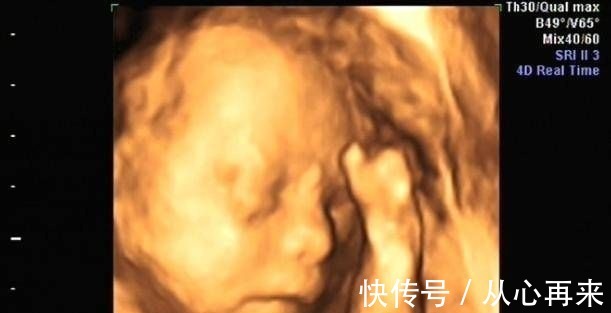

知识要靠聚集才有力量,小编不才,却愿与诸位分享,咱们评论区见今天小编来给大家扒一扒最近的热播剧,小编个人见解,如有错误,欢迎指出哦。每一位女性怀孕的时候,都特别地开心,也会对肚子里的宝宝格外关注,产检有一点点不正常,就会垂头丧气,紧张的不得了。孕期产检,相信不少孕妈妈都很期待四维排畸这一项了,四维彩超排畸检查有不少准妈妈也想带着准爸爸进去,一同分享这其中的喜悦。

但是大部分医院医生都会让准爸爸止步,在等候区等候。小茹怀孕24周左右的时候,身边朋友提醒她这个时候需要做四维大排畸了,不仅能知道胎宝宝发育状况,还可以提前看到宝宝的长相。于是小茹预约了做四维彩超的时间,到做检查的那天,小茹的老公一起陪着她来到了医院,就在小茹老公也准备进去的时候,医生却拦住了他。医生并没有跟他多作解释,做完检查,小茹问了产检医生,才知道医院出于这些原因,不允许家属陪同。这些原因,大家有权利知道1、避免干扰医生工作:多一个人多一个嘴巴,孕妈妈在做四维检查的时候,基本上都会有点紧张和激动的,会不停的询问,这时候如果家属陪同进去,也会跟孕妈妈的心情一样,这时候医生要专心的给胎宝宝做检查,如果回答了你问题,可能会分心,如果不回答,会埋怨医生态度差。还会耽误检查的时间。所以一般医生会拒绝家属陪同。(在这里说一句哦,咱们医院做四维检查是可以家属陪同的哦)